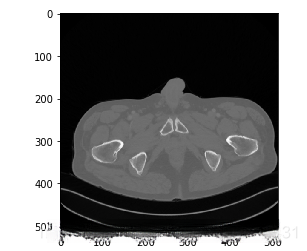

举个例子,CT原图可能是这样的: